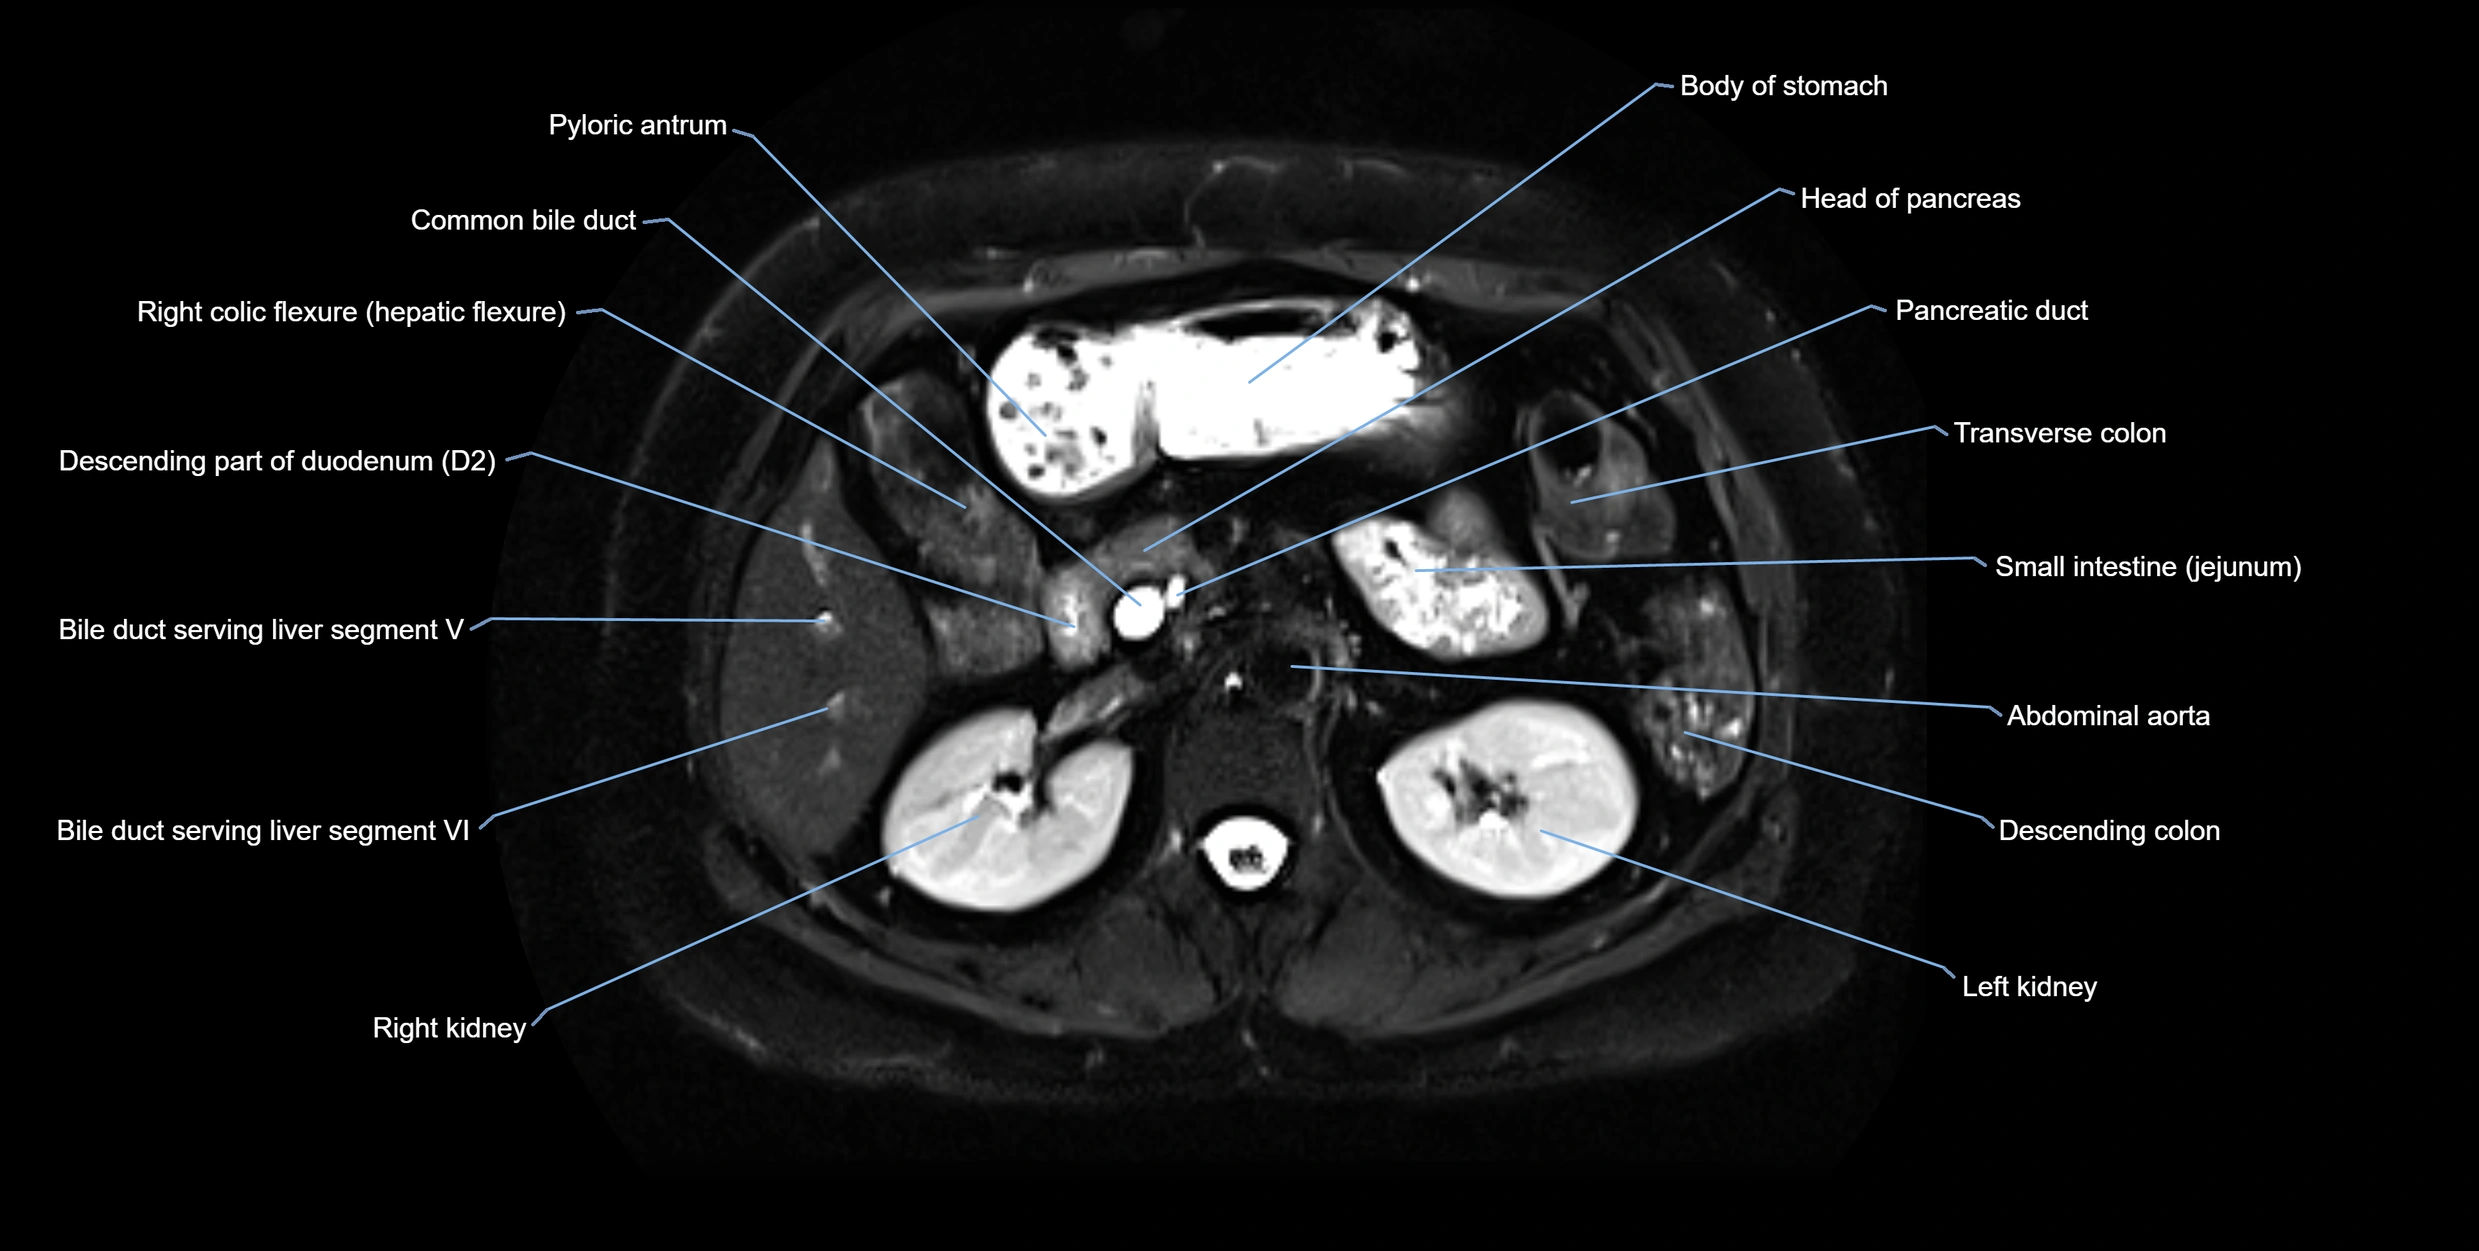

T2-weighted images:

• Duct fluid appears bright

• Accessory duct seen as a fine high-signal tubular structure in pancreatic head

T2 Fat-Saturated HASTE (single-shot):

• Accessory duct: bright, thin linear structure in pancreatic head

• Stones, strictures, or air bubbles appear as dark filling defects

• Excellent for rapid evaluation of duct patency

MRI image

image